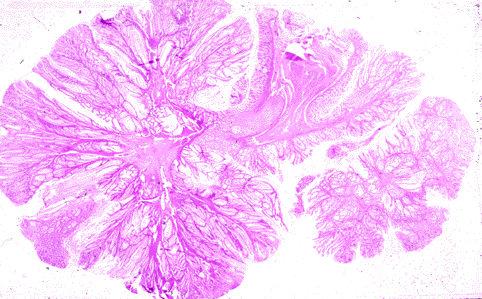

Sindrome de Peutz-Jeghers con 26 años de seguimiento

Tokyo Pref., Centro Nacional de curaciones de Cáncer, Hospital Central y Centro Kyusyu de Curaciones de Cáncerc

[Image-ID:259]

método de exámen

Micro